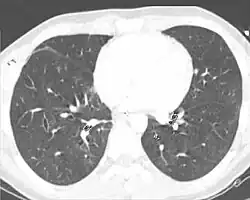

X-ray

Chest X-ray is the most common method used for diagnosis,[42] and may be used to confirm a diagnosis already made using clinical signs.[23] Consolidated areas appear white on an X-ray film.[47] Contusion is not typically restricted by the anatomical boundaries of the lobes or segments of the lung.[31][48][49] The X-ray appearance of pulmonary contusion is similar to that of aspiration,[36] and the presence of hemothorax or pneumothorax may obscure the contusion on a radiograph.[29] Signs of contusion that progress after 48 hours post-injury are likely to be actually due to aspiration, pneumonia, or ARDS.[13]

Although chest radiography is an important part of the diagnosis, it is often not sensitive enough to detect the condition early after the injury.[40] In a third of cases, pulmonary contusion is not visible on the first chest radiograph performed.[10] It takes an average of six hours for the characteristic white regions to show up on a chest X-ray, and the contusion may not become apparent for 48 hours.[10][31][48] When a pulmonary contusion is apparent in an X-ray, it suggests that the trauma to the chest was severe and that a CT scan might reveal other injuries that were missed with X-ray.[2]